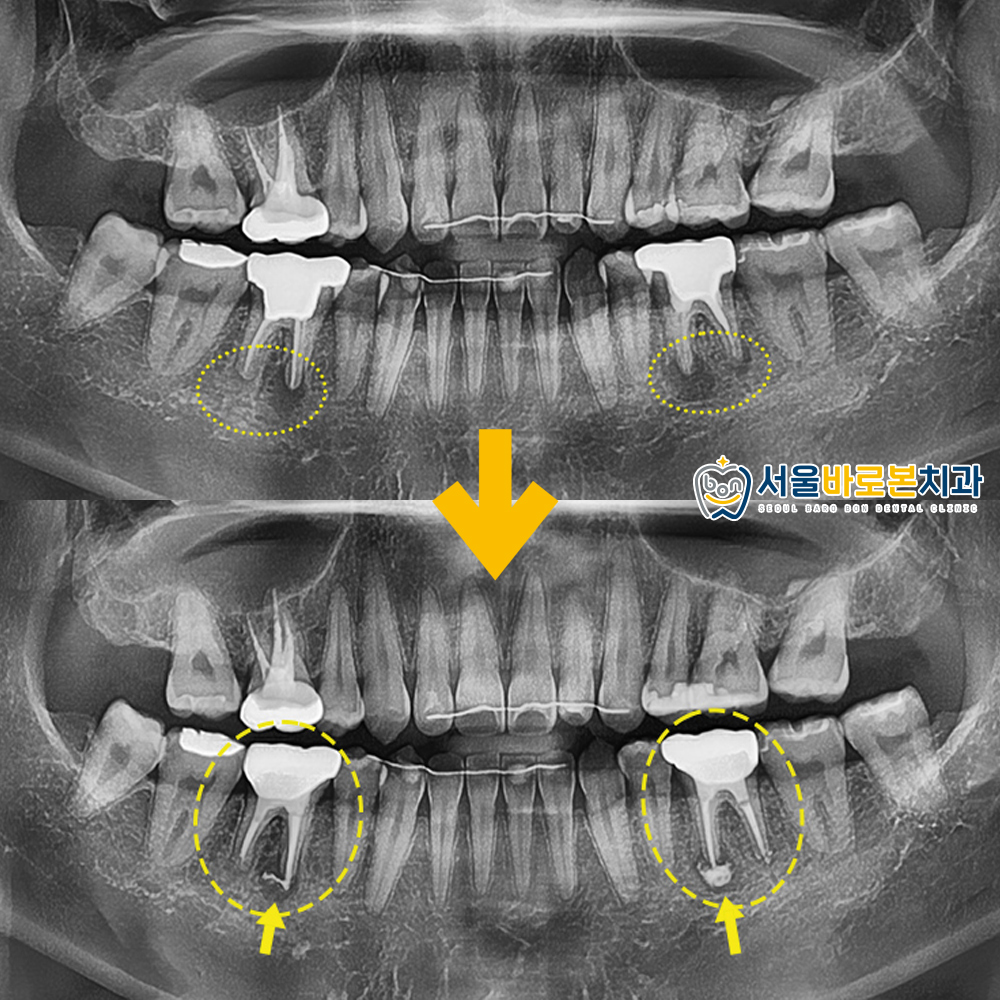

파노라마 사진을 촬영해 확인해보니

과거 신경치료 및 크라운 수복을

받은 상태였고,

뿌리 끝으로 염증이 심한 상태였답니다.

1개월 후 사진 보시면

처음에 비해 염증이 줄어들고

약재들이 잘 자리하고 있는 것을

확인하실 수 있습니다. 🤗